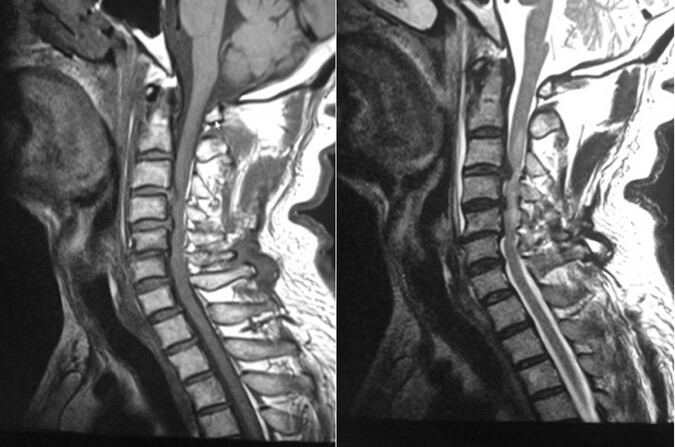

All patients had cervical cord a blurred, high intramedullary signal area at the injured segment only on T2-weighted MRIs at the first examination (Fig. 1). However, at 12 months postoperatively, the blurred high signal area converged to a localized point. Moreover, 10 out of 21 (47.62%) patients with TCSCI and none (0%) of the patients with rp-CSM showed a localized abnormal intramedullary low signal change at the injured segment on T1-weighted MRIs (Fig. 2).

Fig. 1. T1 and T2-weighted MR images before decompression surgery.

Abnormal, blurred intramedullary high-signal area at the injured segment was seen only on T2-weighted MR images.

Fig. 2. T1 and T2-weighted MR images at 12 months postoperatively.

Localized, abnormal intramedullary low-signal are on T1-weighted and a high-signal area on T2-weighted MR images.